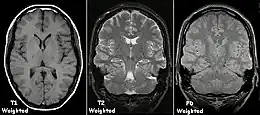

T1 and T2

Each tissue returns to its equilibrium state after excitation by the independent relaxation processes of T1 (spin-lattice; that is, magnetization in the same direction as the static magnetic field) and T2 (spin-spin; transverse to the static magnetic field). To create a T1-weighted image, magnetization is allowed to recover before measuring the MR signal by changing the repetition time (TR). This image weighting is useful for assessing the cerebral cortex, identifying fatty tissue, characterizing focal liver lesions, and in general, obtaining morphological information, as well as for post-contrast imaging. To create a T2-weighted image, magnetization is allowed to decay before measuring the MR signal by changing the echo time (TE). This image weighting is useful for detecting edema and inflammation, revealing white matter lesions, and assessing zonal anatomy in the prostate and uterus.

The standard display of MR images is to represent fluid characteristics in black-and-white images, where different tissues turn out as follows: